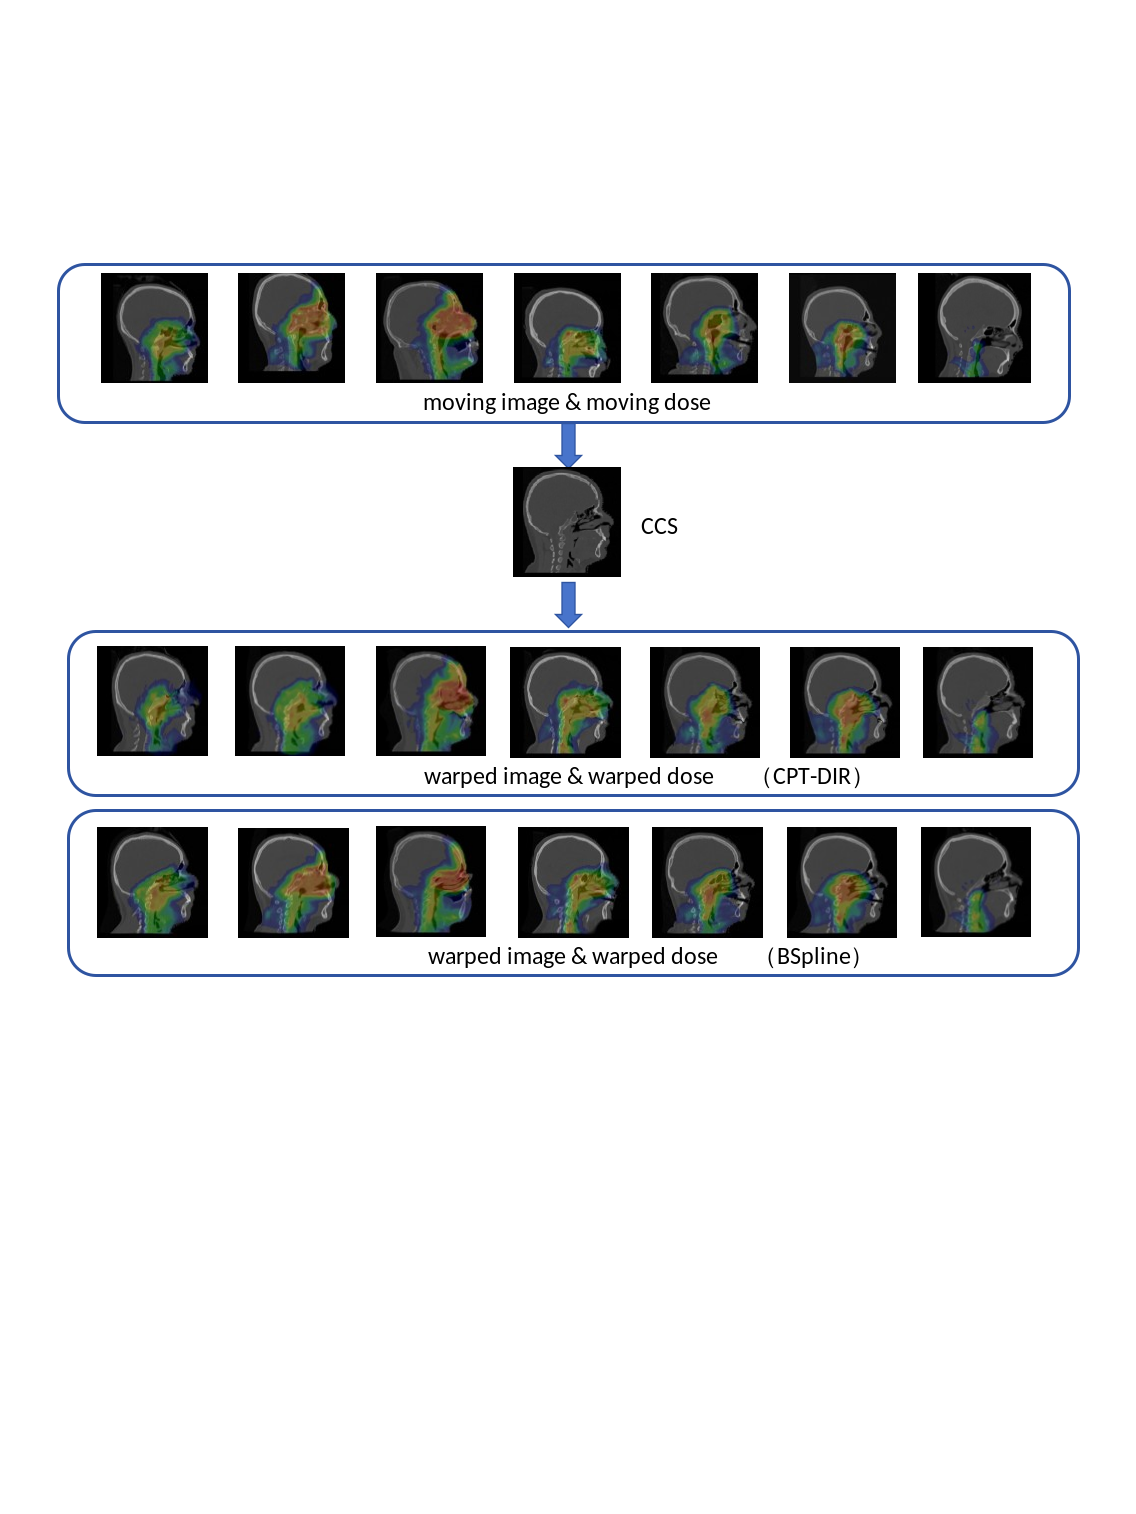

The global registration performance of the two CCSs was quantitatively evaluated and summarised in Table 1. Across all metrics, the contour-informed CPT-DIR consistently outperformed the B-spline in both accuracy and stability. Notably, CPT-DIR reduced the MAE by 44.0%, from 179.1 ± 17.8 HU to 98.9 ± 6.3 HU, and improved the SSIM by 1.3%, from 0.974 ± 0.006 to 0.987 ± 0.002, and improved the PSNR by 22.6%, from 21.292 ± 0.699 dB to 26.107 ± 0.636 dB. OAR contours and dose distributions of the seven patients with IMPT plans were warped to assess the benefit of including brainstem contours as an additional registration constraint, with the CCS1 resulting warped images and brainstem contours demonstrated in Figure 2, CCS2 warped images and warped brainstem contours demonstrated in Figure 3. It compared warped images and brainstem contours between the individual cases and the CCS, demonstrating that integrating the brainstem contour into the loss function significantly improved the DSC scores. Regarding the average results of two CCSs, compared to B-spline (0.604 ± 0.116) and CPT-DIR(wo) (0.621 ± 0.064), CPT-DIR(w) achieved a markedly higher brainstem DSC score (0.878 ± 0.017). For DOO metrics, CPT-DIR(w) (0.753 ± 0.043) also showed significant improvement over both B-spline (0.430 ± 0.117) and CPT-DIR(wo) (0.520 ± 0.085). For the warped brainstem, the HD95 was 2.31 ± 0.60 mm for CPT-DIR(w), compared to 8.98 ± 3.41 mm for CPT-DIR(wo) and 9.73 ± 3.94 mm for B-spline. Detailed HD95 values for the two CCSs were presented in Table 2.

Refer to caption

Figure 1: Overall framework of this study. CT images and bone contours served as default inputs, while brainstem contours were optionally included for a subset of seven patients to evaluate OAR contour registration accuracy in the resulting warped images.

Figure 6: DIR-based warping results: image and dose distribution comparisons for CCS1.